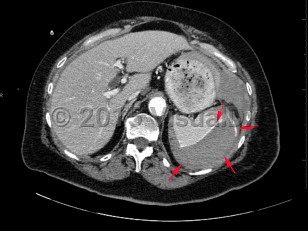

The American Association for the Surgery of Trauma (AAST) has a spleen injury grading system based on imaging and intraoperative findings:

- Grade I: subcapsular hematoma < 10% of surface area; capsular tear; parenchymal laceration < 1 cm depth.

- Grade II: subcapsular hematoma 10%-50% of surface area; parenchymal laceration 1-3 cm in depth that does not involve a trabecular vessel.

- Grade III: subcapsular hematoma > 50% of surface area or expanding ruptured subcapsular or intraparenchymal hematoma; intraparenchymal hematoma > 5 cm in diameter or expanding; parenchymal laceration > 3 cm in depth or involving trabecular vessels.

- Grade IV: laceration involving segmental or hilar vessels producing major devascularization (> 25% of spleen). Grade V: completely shattered spleen; hilar vascular injury devascularizes spleen.